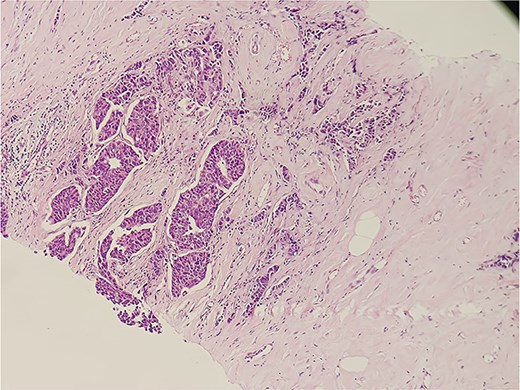

Mammography revealed an asymmetrical density in the upper outer quadrant of the right breast with BIRADS V classification. Ultrasonography identified an irregular hypoechoic lesion measuring 3.8 × 2.5 cm in the right breast. Additionally, multiple enlarged axillary lymph nodes with cortical thickening were seen, the largest measuring 1.02 cm in diameter. A core needle biopsy of the breast lesion demonstrated features of invasive carcinoma, not otherwise specified (NOS), Grade II based on the Nottingham grading system. Immunohistochemistry revealed the tumor to be ER-positive (78%), PR-negative, Her2Neu-negative, and Ki67–21%, confirming it as Luminal A subtype. The excised axillary lymph nodes exhibited caseating granulomatous inflammation, consistent with tuberculosis (Fig. 1). Acid-fast bacilli (AFB) testing further confirmed the diagnosis of TB. Pre-surgical imaging revealed metabolically active areas in the breast lesion and axillary lymph nodes with no evidence of systemic metastases (Figs 2 and 3).

Histopathological slide section of biopsy specimen taken from the right axillary node lesion showing caseating granulomatous inflammation, consistent with tuberculosis.